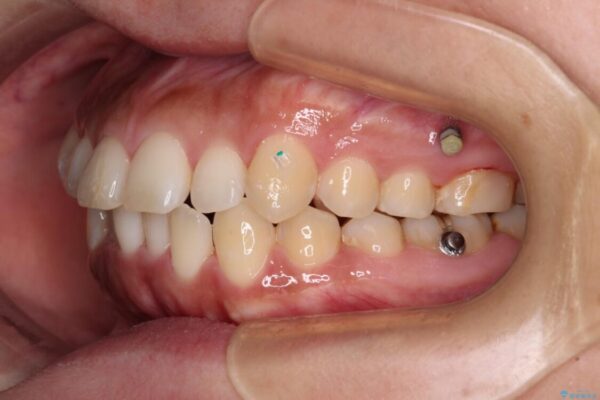

治療途中

• 【モニター】カリエール・ディスタライザーを併用した八重歯のインビザライン矯正 治療途中画像